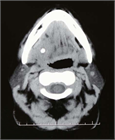

1. 唾石に伴う口底の発赤、腫脹および疼痛がある場合、抗生剤、抗炎症鎮痛剤を投与することが推奨される(推奨度1)

1. 口底に限局した導管内前方部唾石の診断に対し、咬合法X線画像検査が推奨される(推奨度2)